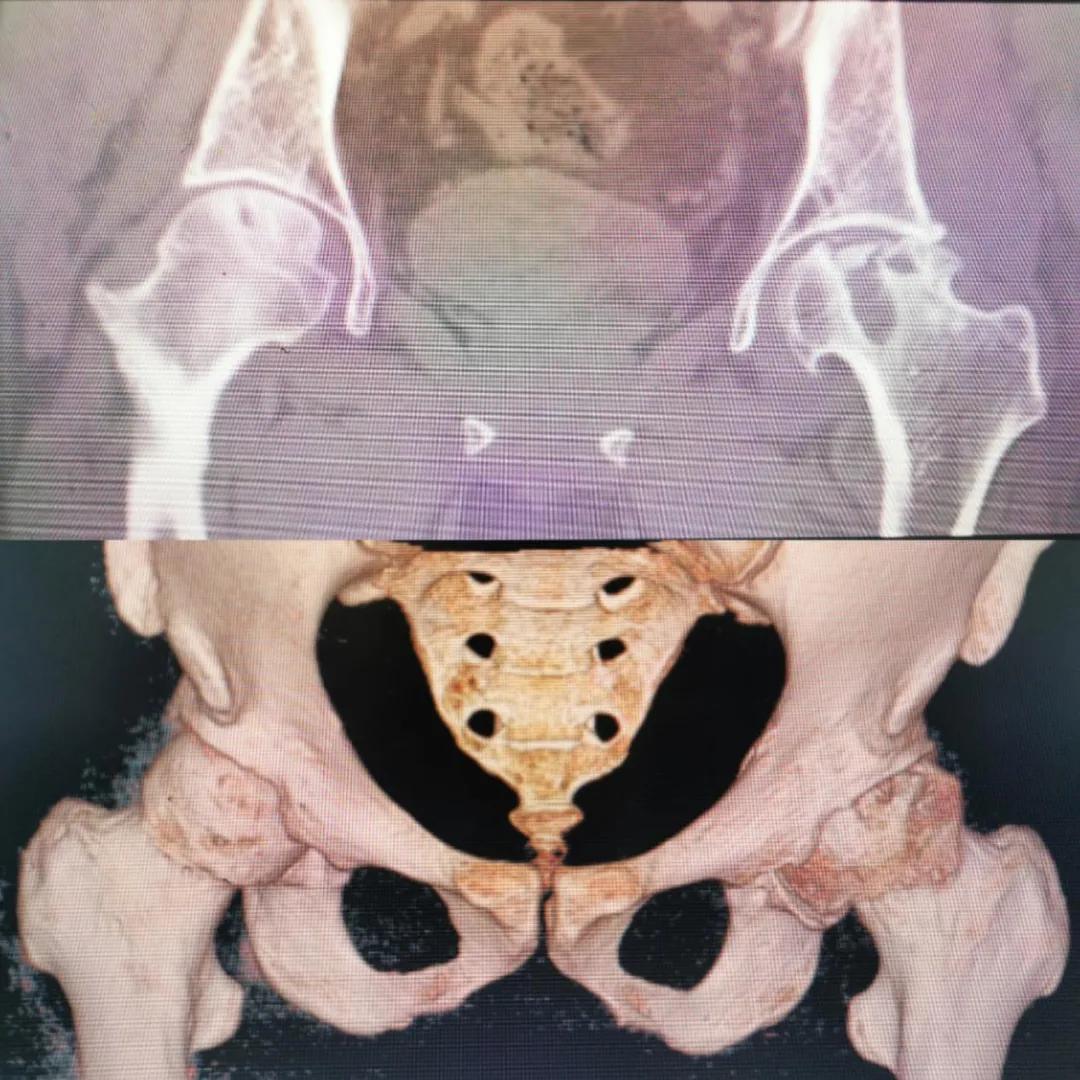

入院急查血結(jié)果提示炎癥反應(yīng),感染較重,凝血功能及肝功均不同程度損害;髖關(guān)節(jié)磁共振(MRI)檢查提示雙側(cè)股骨頭缺血壞死,繼發(fā)髖關(guān)節(jié)炎,左側(cè)髖周軟組織腫脹。醫(yī)療團(tuán)隊(duì)給出的初步診斷為膿毒血癥、股骨頭缺血性壞死、軟組織感染、皮膚潰瘍及閉孔神經(jīng)損傷。

圖片(圖為患者入院時(shí)髖部CT檢查)

追溯病史,患者訴前不久曾用蜂蜇療法治療股骨頭壞死,每日4次,每次100只蜜蜂蜇雙臀部、髖部,這才導(dǎo)致了病情急劇進(jìn)展。查明了來(lái)龍去脈,我院智能微創(chuàng)骨科醫(yī)護(hù)團(tuán)隊(duì)與患者家屬積極溝通病情,給予特殊級(jí)抗生素抗感染以及消腫、止痛等支持治療,同時(shí)對(duì)潰瘍創(chuàng)面進(jìn)行專(zhuān)業(yè)、規(guī)范的清創(chuàng)、換藥處理,保護(hù)創(chuàng)面降低感染程度;護(hù)理上輔助翻身,減少壓力性損傷。